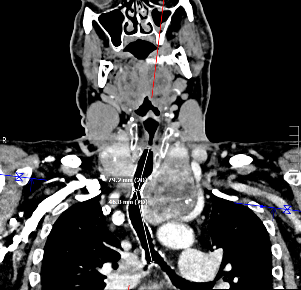

Zwei farbkodierte 3D-Impedanzplanimetrie-Darstellungen (EndoFLIP) einer Ösophagusstenose bei 40 ml Füllvolumen: links „Prätherapeutisch“ mit starker Mitteneinschnürung, rechts „Posttherapeutisch“ mit abgeschwächter Einschnürung.

Quelle: Prof. Benjamin M. Walter, Universitätsklinikum Ulm

Ergebnis: EndoFLIP ermöglichte die prä- und posttherapeutische Visualisierung der Stenosekonfiguration. Die Dilatation wurde durch die Zunahme des minimalen Öffnungsdurchmessers (p=0,003), der minimalen Querschnittsfläche (p=0,003) und des Distensibilitätsindex (p=0,004) quantitativ erfasst. In der Planimetriegruppe wurde die Stenoselänge im Vergleich zu den EndoFLIP-Messungen endoskopisch um durchschnittlich 14,4 mm unterschätzt (95%-KI: 12,5–16,4 mm). Der auf dem Bougiedurchmesser basierende posttherapeutische Öffnungsdurchmesser lag im Mittel um 1,2 mm über der EndoFLIP-Messung (95%-KI: 0,4–1,8 mm). Nach 14 Tagen zeigte die Planimetriegruppe (56 auf 61 Punkte, p=0,005) eine ausgeprägtere Symptombesserung als die Kontrollgruppe (42 auf 44 Punkte, p=0,176). Die Aufnahmefähigkeit fester Nahrung verbesserte sich in der Planimetriegruppe von 9,1% auf 63,6% (p=0,014) und in der Kontrollgruppe von 12,5% auf 25,0% (p=0,317).

Schlussfolgerung: EndoFLIP ermöglichte eine standardisierte und strahlungsfreie Beurteilung komplexer Ösophagusstenosen. Der Einsatz einer 3D-Impedanzplanimetrie kann dazu beitragen, die Therapie komplexer benigner Stenosen des oberen Gastrointestinaltrakts zu optimieren.